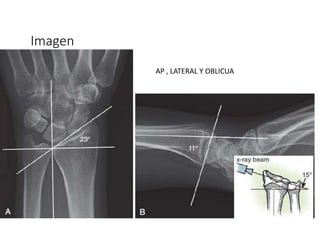

Imagen

AP , LATERAL Y OBLICUA

23° 11°

Goniometria

10mm 1-2mm

Diagnóstico: Radiológico

RX AP + LATERAL

AP

Acortamiento

radial

Inclinación radial 23

grados

Desplazamiento

Plano Sagital

Inclinación

Diagnóstico: Radiológico RX AP+ LATERAL AP Acortamiento radial Inclinación radial 23 grados Desplazamiento Radial Plano Sagital Inclinación Radial Desplazamiento TAC Fracturas intrarticulares Detectar hundimientos No congruencia Lesiones asociadas. RMN Lesiones ligamentares Fx Escafoides.